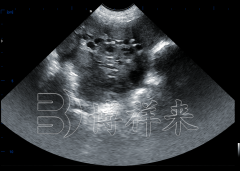

吉彩网一、什么是 猪卵泡检测B超机 ? 猪用B超机是一种专业兽用超声设备,采用B-mode(二维)超声技术,配合高频探头(如3.5 MHz、5 MHz或7.5 MHz),主要用于监测母猪卵泡发育、估测排卵……

吉彩网在规模化猪场生产中,如何科学划分批次、精准把控母猪生理状态,是提升猪场生产效益的关键。猪用B超机通过实时监测卵泡发育、同期发情与胎仔数量,为猪场批次化管理提供了可靠……